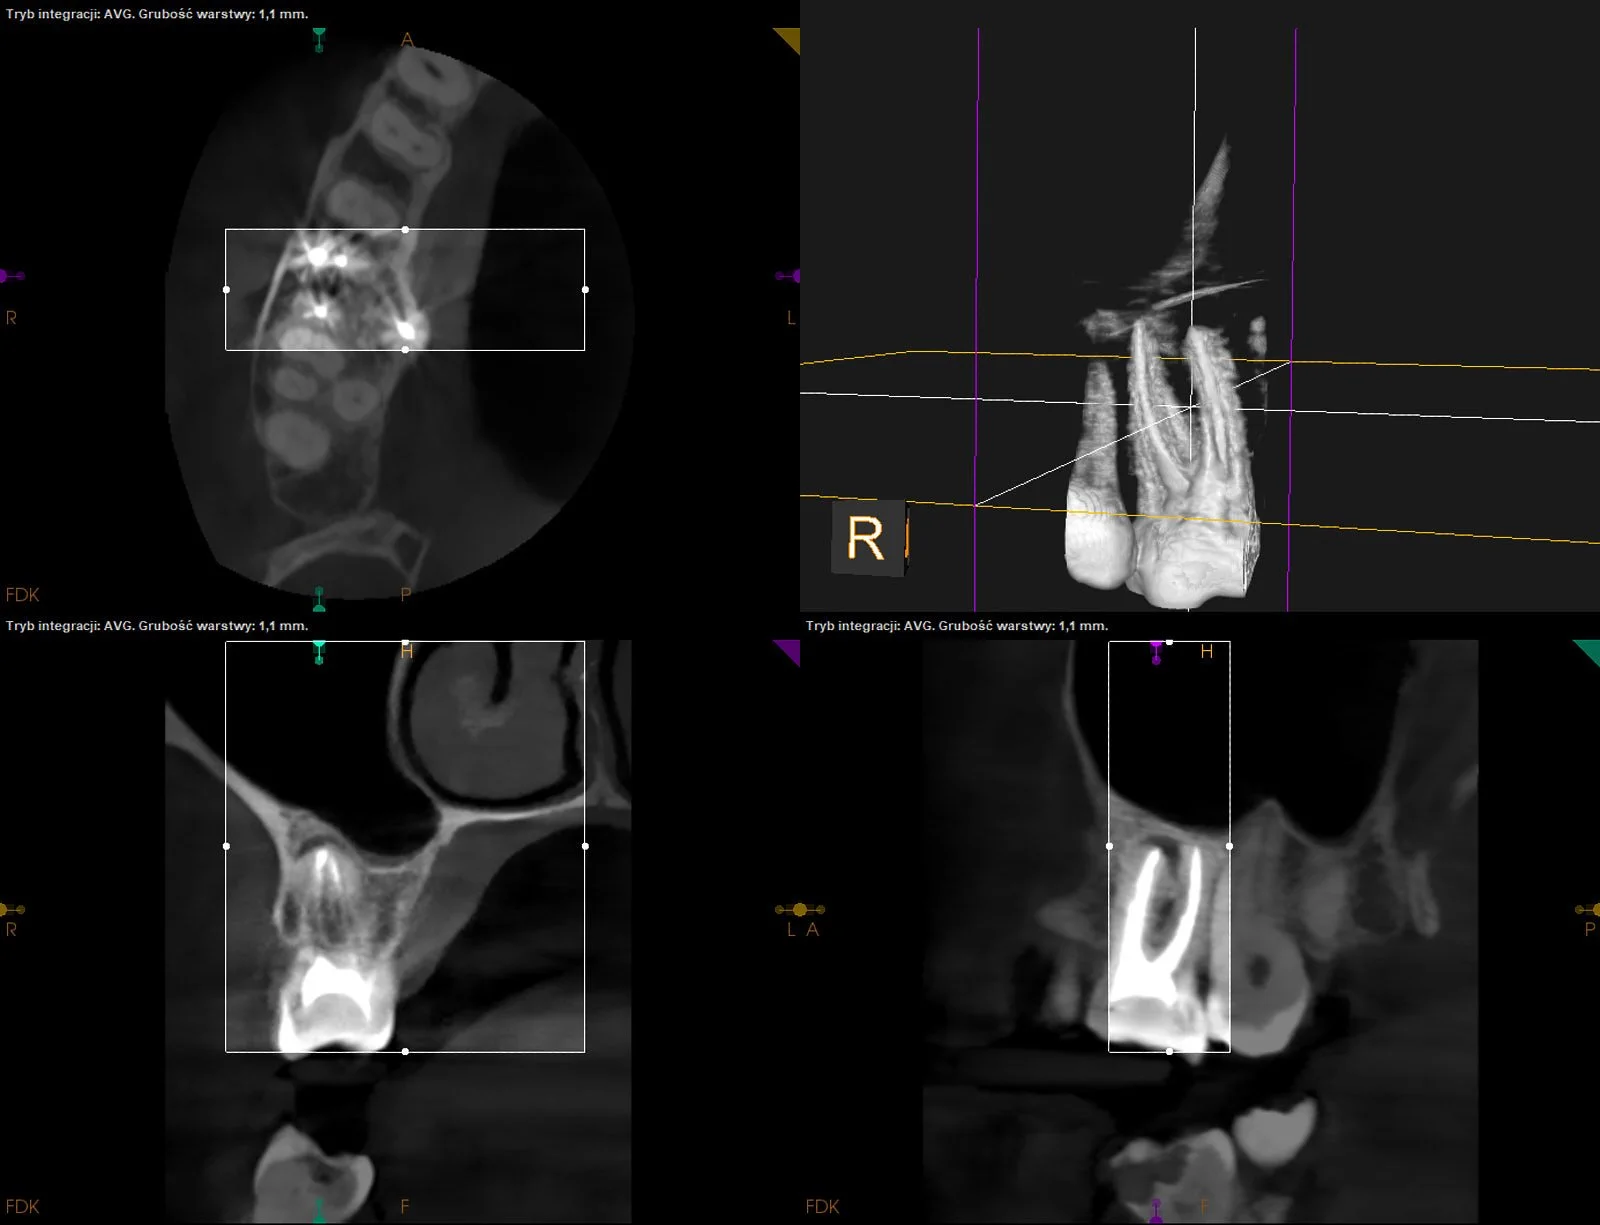

CASE STUDY VII

Gojenie okolicy okołowierzchołkowej przy korzeniu mezjalnym i dystalnym d.26 po ponownym leczeniu kanałowym (z uwagi na open apex w kanale dystalnym wykonano zamknięcie cementem MTA).